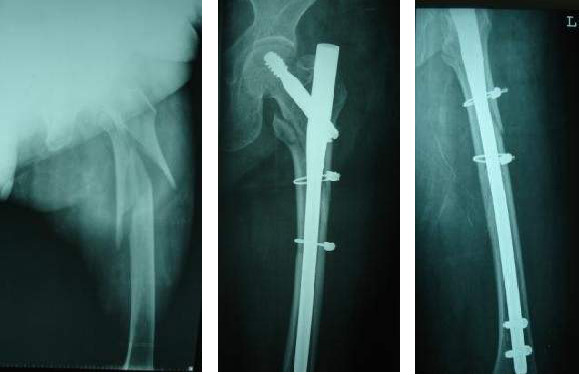

Un clou de plus petit diamètre (généralement 9 mm) peut être enfoncé sans dilatation.(au-dessus de l'extrémité caudale la plus épaisse du clou Gamma - 17 mm)

L'extrémité proximale du PFN a une cambrure approximative de 6 degrés, réduisant l'angle de valgus et éliminant le besoin d'une forte rétraction interne pendant la traction.

L'extrémité supérieure permet la mise en place de deux vis dans la tête fémorale, avec l'ajout d'une vis anti-rotation et d'un double appui de clou dans le col fémoral, ce qui augmente la résistance à la fatigue.

La distance entre le trou de verrouillage distal et l'extrémité distale du clou principal (extension conique) est plus longue, ce qui peut réduire la concentration de contraintes dans la tige fémorale.

Relativement moins de traumatismes.

Il s'agit d'une méthode de fixation intramédullaire mini-invasive avec une petite incision et un traumatisme minimal.